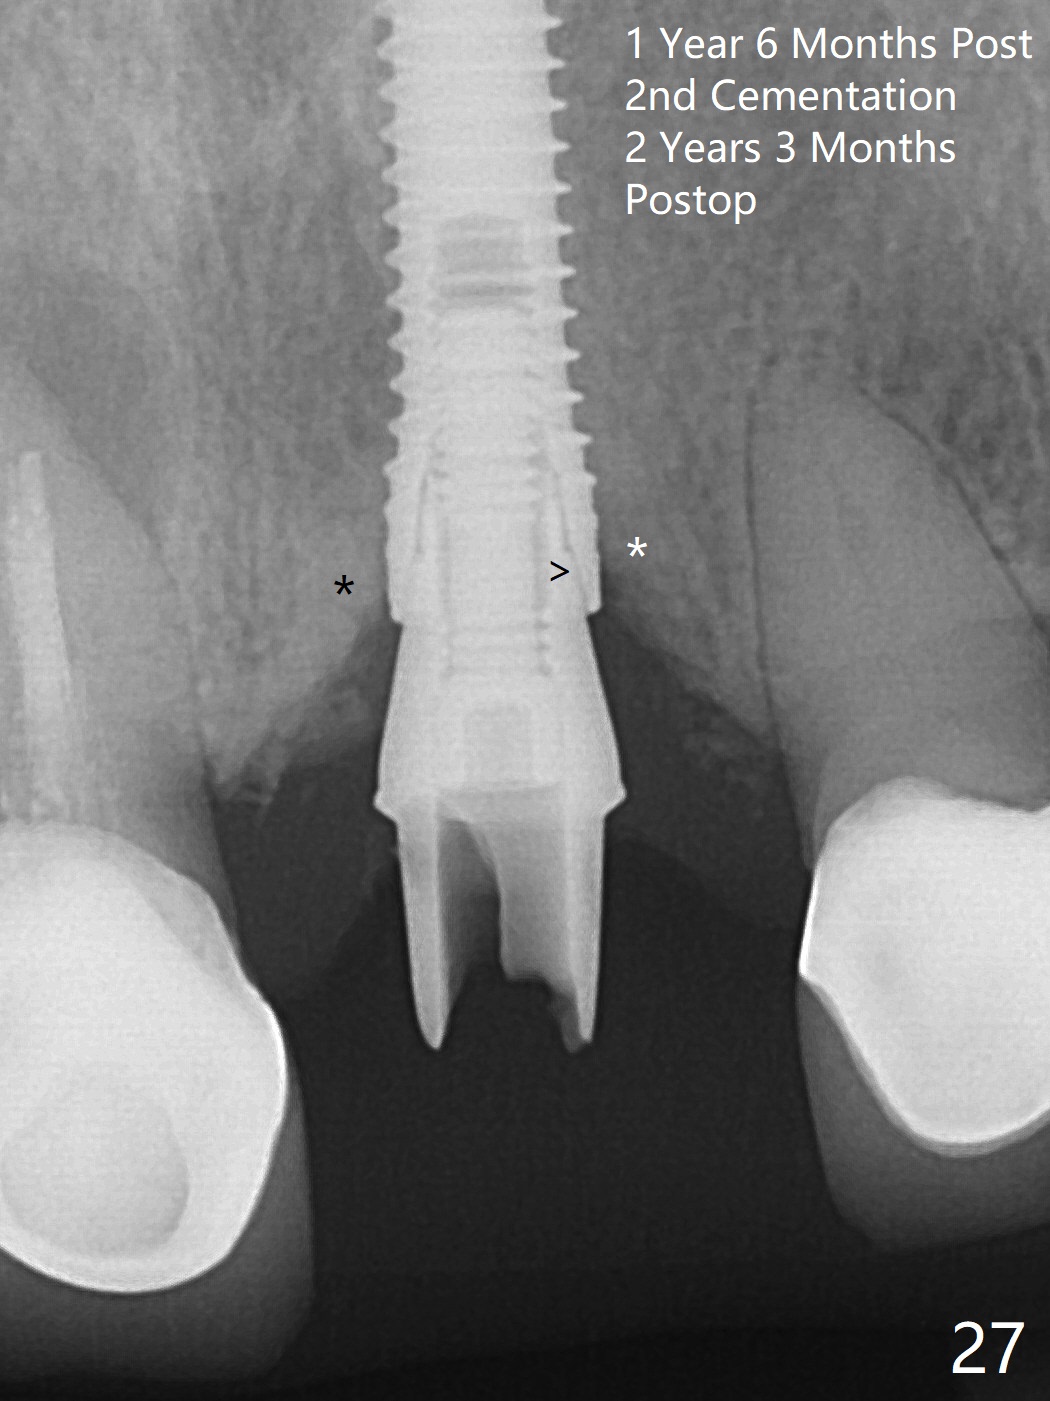

The buccal contour at #9 seems to be slightly concave preop (Fig.1,2 (*)). In fact the buccal plate is found to be lost when the tooth is extracted. Osteotomy is initiated as palatal as possible apical, but the occlusion dictates the coronal end of the osteotomy should be buccal, leaving the buccal gap ~ 2 mm for bone graft. The initial osteotomy (18 mm deep) appears to be close to the Incisive Foramen (Fig.3 blue dashed line). The nasal floor appears to be intact when the drill is removed. Subsequent osteotomy is adjusted so that the apical end of the osteotomy moves distal; when a 3.8x15 mm dummy implant is partially placed, there is clearance (Fig.4). It remains so when a definitive implant is seated (Fig.5); Vanilla graft is placed (Fig.5 *) before placement of a 4.5x5.5(3) mm abutment. More allograft is placed when an immediate provisional is fabricated (Fig.6 arrow and *). The gingiva remains to be recessive 1 month postop (Fig.7). It seems to be related to the bulky gingival margin of the provisional (Fig.8 *). After trimming the latter (Fig.9 *), the gingival margin immediately returns close to normal (Fig.10). The gingival margin is even between #8 and 9 two months postop, but the bone graft is exposed apically (Fig.11 ^). It may heals by itself. Otherwise debridement, regraft, PRF and suture are pending. The coronal portion of the socket heals 4 months postop (Fig.12). The gingival cuff forms by the immediate provisional (which is removed for impression) 4 months postop (Fig.13 *). While the full Zirconia crown at #7 remains intact (Fig.14), the PFM at #9 has porcelain chip (Fig.15). It is partially due to the occlusion; while the crown at #7 has clearance with the opposing dentition (Fig.16 *), the one at #9 has no. The access hole at #9 (Fig.17 *) seems to weaken the crown structure. There is no access hole at #7. No solid posterior support is another contributing factor for chip (Fig.18). The buccal plate has mild atrophy at #7 and 9 (Fig.19 *). A piece of bone graft is being expelled apically at #9 (Fig.20 >) and is removed subsequently (Fig.21). Before impression for repacking porcelain, the opposing incisal edge has been shortened (Fig.22 arrows, as compared to Fig.16). Since the ideal access hole is at the incisal edge (Fig.25 black circle), buccal to the existing one (Fig.24 A), the abutment is torqued before the repaired crown is recemented (Fig.23). Finally the crown has occlusal clearance (Fig.26). Porcelain chips again around the access hole of PFM 1.5 years post 2nd cementation. The dense bone at the crest (*) cannot explain why the abutment is not loose, since it remains incompletely seated (>). As it was trimmed short, an angled abutment is used (Fig.28). The coronal end is lingual, while #9/24 is edge to edge. The lingual aspect of the coronal end of the abutment is heavily trimmed to reduce bulkiness. To prevent chip, Zirconium crown will be fabricated in spite of the fact that it does not match the PFM of #8 (potential shade discrepancy). The patient is pleased with the new Zirconia crown (Fig.29).